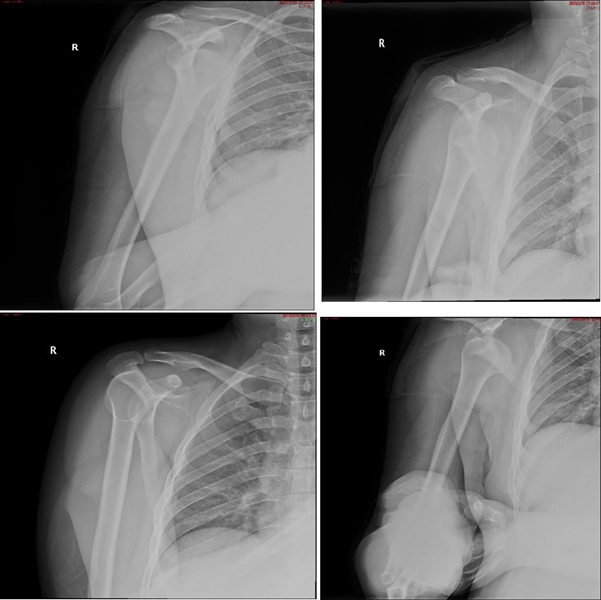

典型病例,王XX,男性,15岁。主诉右肩外伤疼痛、活动受限1月。既往半年前有肩关节脱位病史。

图37 既往肩关节脱位时,急诊所拍的X线片

图38 复位后的肩关节CT

视频6-7(拼在一个画面里,左右并排) 术前查体,ISIS评分6分

图39 此次复发脱位MR评估

图40 影像学评估

双侧CT三维扫描显示:D=34mm,d=3mm,d/D=肩胛盂骨缺损9%;GT=25.2mm,HIS=30mm。

该患者为轨迹外Hill-Sachs损伤,需要做bankart修补,同时轨迹外做remplissage手术。